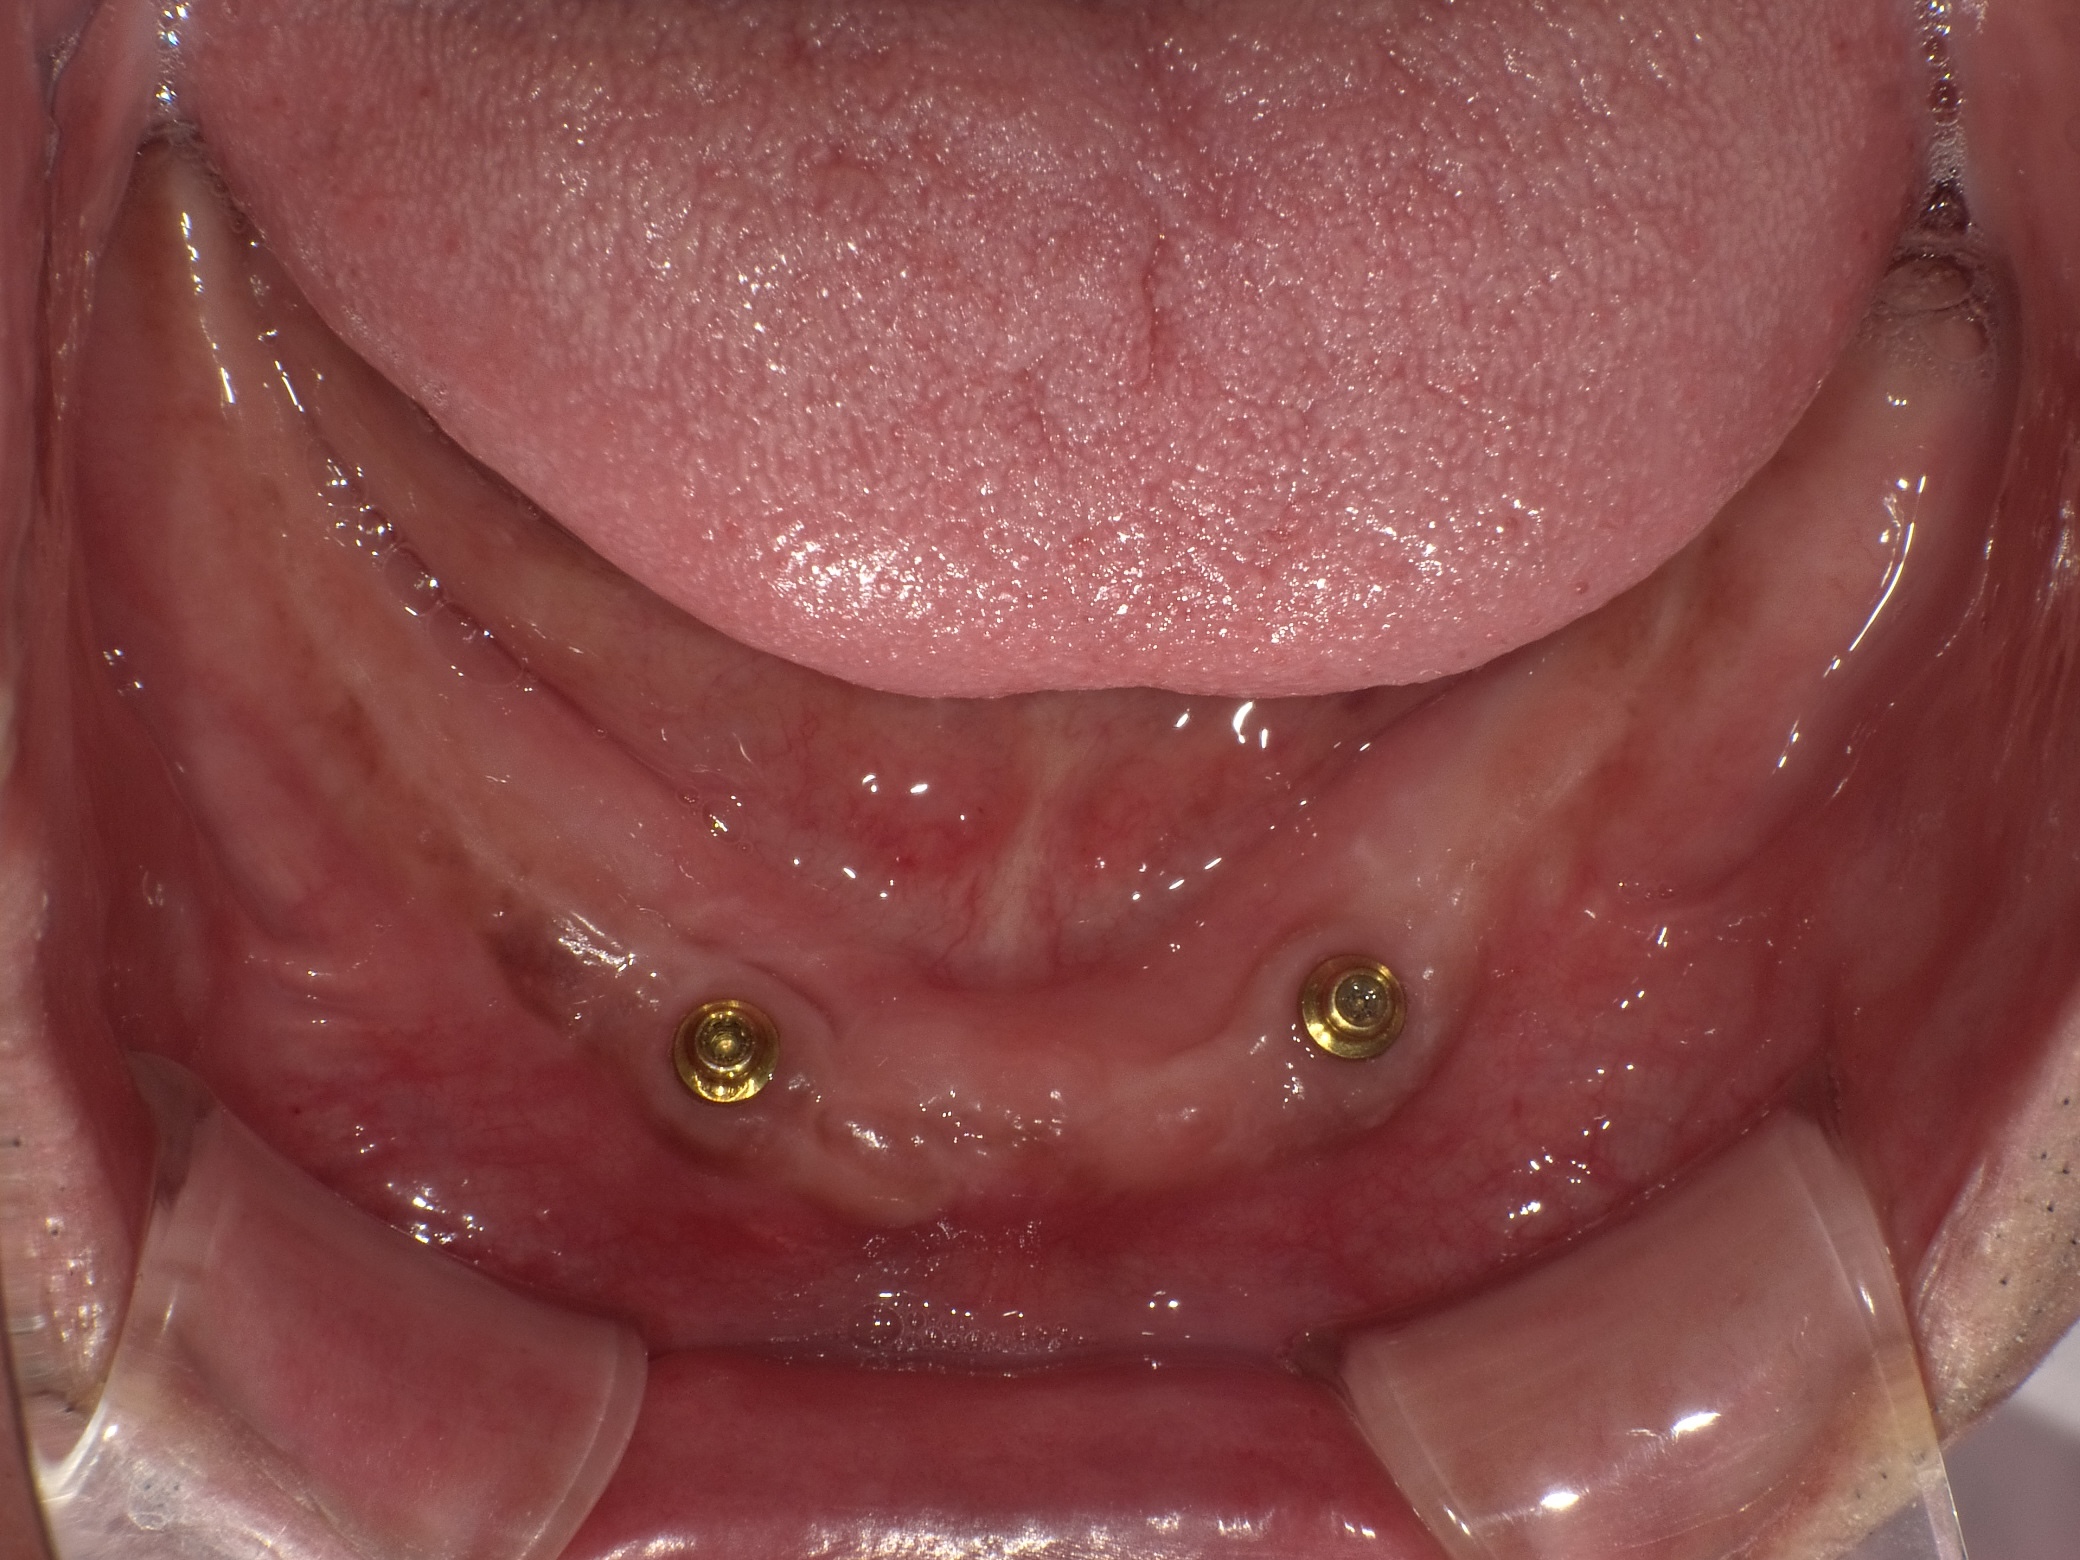

インプラントオーバーデンチャー症例

主訴 しっかり噛んで美味しいものを食べたい(男性) 治療内容 保存不可能な歯を抜歯後、2本のインプラントを埋入。

インプラントのアタッチメントと入れ歯の留め具とで凹凸接続し、動かない快適な入れ歯を装着しています。治療期間 約4ヶ月 費用 総額 ¥880,000–(税込) リスクと副作用 ・外科治療となるので、お身体の状態によっては受けれない場合がある(広範囲に適用可能な治療ですが、個々の患者様の状況によって適用外な場合もある)

・術後に多少の痛みや腫れが出ることがある